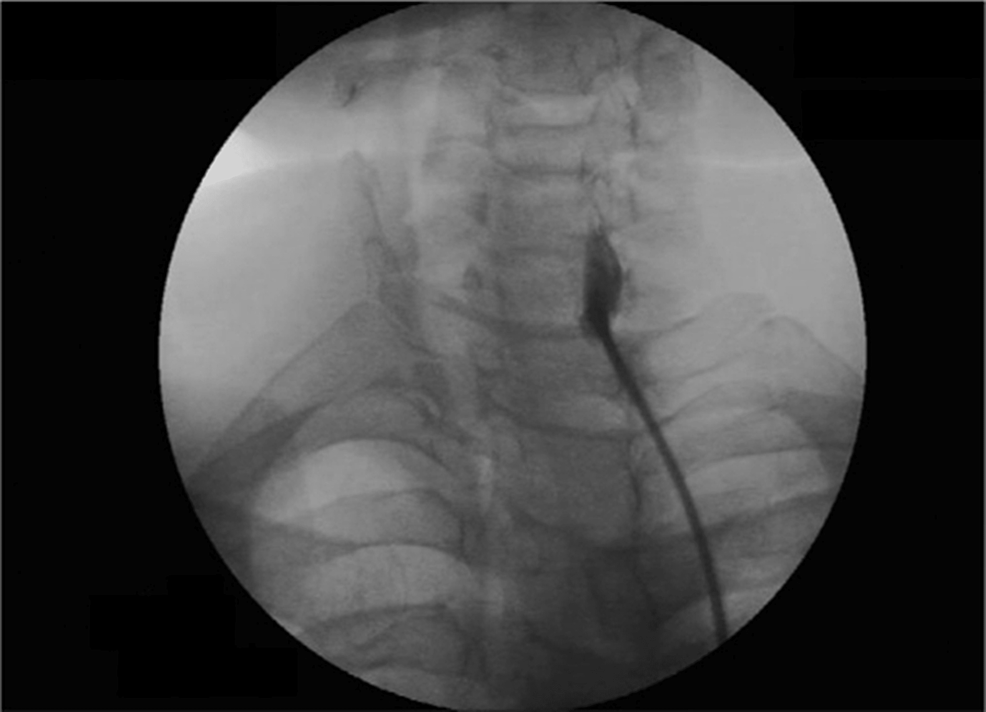

Fluoroscopy images of PDN placement. (a) A guidewire is passed along